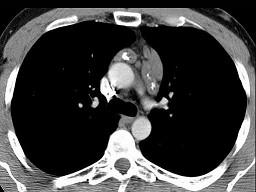

问题 21岁,女,颈部淋巴结肿大,无压痛,请结合CT检查选出最可能的诊断 ( )

选项 A、转移性淋巴结肿大 B、间皮囊肿 C、淋巴结核 D、结节病 E、淋巴瘤

答案 E